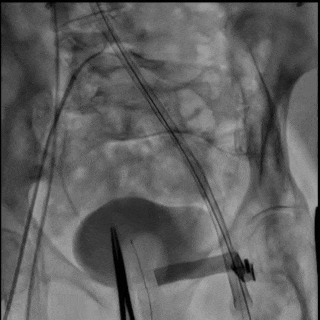

图6 逐步操作过程

(A)使用 21 mm TRUE balloon 行主动脉瓣预扩张。于钙化的 Evolut R valve 瓣叶水平可见明显“球囊腰征”(白色箭头),提示充盈过程中存在显著阻力。(B)植入 23 mm SAPIEN 3 Ultra RESILIA valve(S3UR)过程中发生球囊破裂。球囊远端可见造影剂积聚(白色箭头),形成类似“伞状”外观,提示存在水平撕裂。23 mm 瓣膜未完全释放(白色箭头)。(C)对侧入路行髂动脉造影。可见左侧髂总动脉夹层,但无活动性造影剂外渗(白色箭头)。(D)使用 23 mm TRUE balloon 对未完全扩张的 S3UR 瓣膜进行后扩张。(E)血管内干预后髂动脉造影。将 16F eSheath 回撤至左侧髂外动脉,并于夹层的髂总动脉内植入一枚 8 × 59 mm VBX 覆膜支架(白色双向箭头)。(F)血管内干预后股动脉造影。左侧股总动脉穿刺通路采用 7 × 50 mm Viabahn stent graft 进行封闭(白色双向箭头)。最终造影显示无造影剂外渗,血流通畅。

经左股动脉将输送系统及鞘管整体取出,随后更换为16F 鞘管以压迫可能的血管损伤。经对侧髂动脉造影显示左侧髂总动脉夹层,但无活动性造影剂外渗(图6C,视频8)。术中血流动力学始终稳定。

将16F鞘管回撤至左髂外动脉水平,并植入一枚8×59mm VBX 覆膜支架用以修复左侧髂总动脉夹层(图6E,视频10和11)。左股动脉穿刺口采用7×50mm Viabahn 覆膜支架进行封闭(图6F,视频12)。最终造影示无造影剂外渗,血流通畅(视频13)。